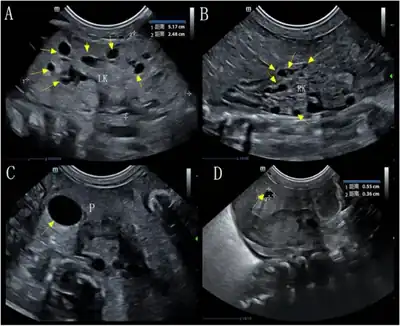

a,b)Image upper abdomen showed left & right kidney multiple cysts c,d) pancreas contained two cysts